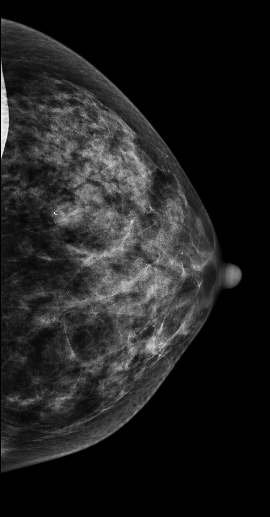

DBT图像:

在常规2D图像右乳外上象限隐约见一不规则团块影,部分边界模糊(容易漏掉),边缘可见粗大钙化灶,在V-Preview图像MLO位和CC位上团块显示较模糊,但钙化清晰可见,在3D-slab图像上我们可以清晰见到病灶呈分叶状改变,边缘可见蛋壳样钙化灶,周边见细线样透亮环。从以上细微征象我们可以初步判断是一良性病灶。

病理证实左乳纤维腺瘤,此病例我们可以发现3D-Slab(厚层图像)对钙化灶形态大小显示更加清晰。